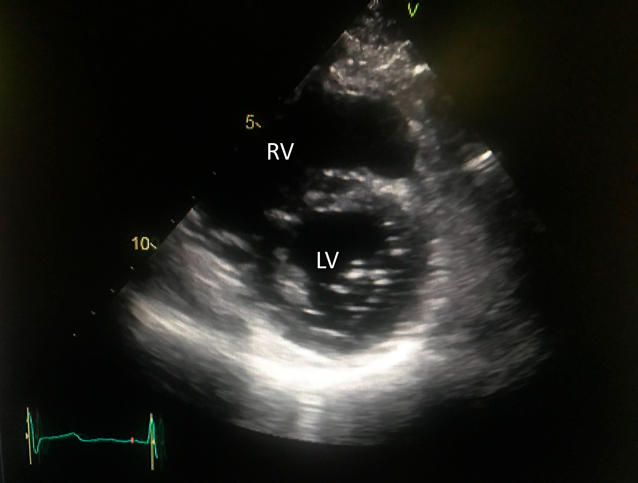

The PAH drugs were resumed, in the same doses as preoperatively administered, via a gastric tube from the first postoperative day. After iNO ceased, the patient was weaned off mechanical ventilation on the second postoperative day. On the following day, oral intake was restarted, and oral warfarin was prescribed for anticoagulation therapy. Inotropic support was gradually decreased and stopped on the 5th postoperative day. On the 6th postoperative day, nasal oxygen cannula was removed, and he was discharged from the intensive care unit to a general ward. Postoperative enhanced CT revealed that the neo-SVC and the PV routes had no obstruction (Fig. 5). Electrocardiogram showed sinus rhythm. Transthoracic echocardiography suggested that blood flows across the right PVs and the SVC had been well established, and that PAH had improved (Fig. 6), Thereby the patient was discharged home on the 16th postoperative day. His clinical status improved to NYHA functional class I. He returned to his work at 2 months after surgery. The dosage of selexipag was gradually weaned according to the echocardiographic findings. We performed RHC at 15 months after surgery, which showed that mean PAP decreased to 34 mmHg. Macitentan and tadalafil were continued although selexipag was changed to beraprost due to adverse effects such as diarrhea and face flushing.

Fig. 6 Postoperative transthoracic echocardiogram

The left ventricle is less deformed in the short axis view. LV, left ventricle; RV, right ventricle.